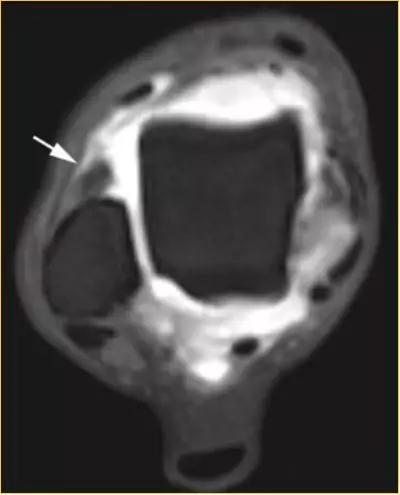

1.前外踝撞击综合症:

- 踝关节旋后损伤通常导致距腓前韧带、跟腓韧带以及前外侧关节囊撕裂合并关节内出血,继而产生瘢痕组织或滑膜增生肥厚。常伴距骨顶部外前部分的软骨侵蚀及后胫腓韧带和骨间膜损伤。需与跗骨窦综合症鉴别。

- 影像学表现为外侧沟内异常软组织或(和)前胫腓韧带(AITFL)异常肥厚。

- 因为炎症组织在关节镜下的形态类似膝关节的半月板,所以又称为“半月板样损伤”。

①踝关节外侧沟内异常软组织